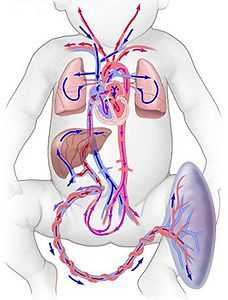

Начинается кровообращение с пупочной вены, которая впадает в печень. Из органа кровь поступает в венозный или аранциев проток, сообщающийся с нижней полой веной.

Аномалии строения сосудов у ребенка могут приводить к врожденным порокам развития сердечно-сосудистой системы.

Из нижней полой вены кровь переходит в правое предсердие, а затем в одноименный желудочек. Отсюда она попадает в легочной ствол, отходящий к легким. Часть крови через овальное окно напрямую попадает из правого предсердия в левое. Из него — в левый желудочек и аорту.

Так как органы дыхания у плода не функционируют, они не нуждаются в кровоснабжении. Поэтому кровь из легочного ствола через Боталлов проток устремляется в аортальный сосуд. Он, благодаря своим ветвям, кровоснабжает все внутренние органы и структуры нервной системы.

Венозная кровь собирается в пупочную артерию, которая вновь направляется в плаценту. На этом круг кровообращения плода замыкается.

Внутриутробное развитие плода и кровоток через плаценту приводят к тому, что часть сердечно-сосудистой системы у ребенка имеет отличия от организма взрослого. Это влияет и на функционирование органов. Отличительные черты кровообращения следующие:

- артерии и вены устроены таким образом, что кровь, богатая кислородом и питательными веществами, напрямую попадает в организм и артериальные сосуды плода. Это обеспечивает насыщение плазмы кислородом и питательными молекулами;

- малый круг кровообращения, обеспечивающий у взрослого человека поступление в кровь кислорода, не работает. Это следствие отсутствия у ребенка легочного дыхания;

- более 95% крови находится в большом круге кровообращения. Подобное состояние связано с наличием овального окна и Боталлова протока;

- давление в магистральных сосудах (легочной ствол и аорта) низкое и находится на одинаковом уровне, так как они сообщаются друг с другом.